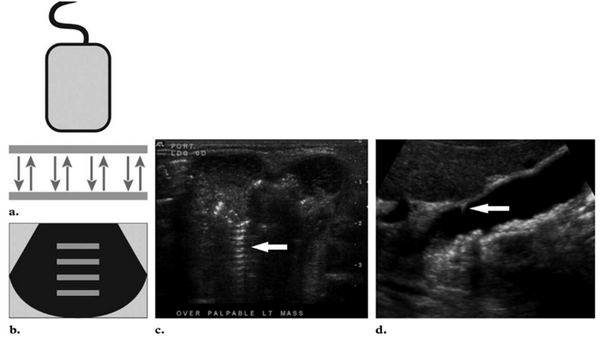

Помехи - это искажение изображения, вызванные воздействием внешних причин на УЗИ-аппарат. Существует много разновидностей помех, из них мы выделили наиболее часто встречающиеся:

- сетевые - вызванные включёнием одновременно с УЗИ-аппаратом электрических приборов и сотовым телефоном (Рис.1; 2);

- вызванные плохим качеством выбривания кожи животного (Рис.3);

- вызванные недостаточным количеством УЗИ-геля, нанесённого на кожу (Рис.4) ;

- вызванные движениями животного, в том числе дыхательной экскурсией (Рис.5).

Рис1. Помехи, вызванные включённым рядом с аппаратом УЗИ сотовым телефоном. Во избежание этого лучше просить владельца выключать сотовый телефон при проведении ультразвукового исследования.

Рис2. Помехи, вызванные работающими электроприборами, включёнными в сеть рядом с аппаратом УЗИ.

Рис3. Помехи, вызванные плохим выбриванием животного (продольные полосы слева).

Рис 4. Недостаточное количество геля при проведении УЗИ (правая половина снимка).

Рис. 5. Помехи, вызванные дыхательными движениями животного.

Как представлено на фотографиях, помехи ухудшают качество изображения и не редко препятствуют тонкой и детальной визуализации исследуемой структуры. Соответственно помехи при проведении УЗИ следует сводить к минимуму.